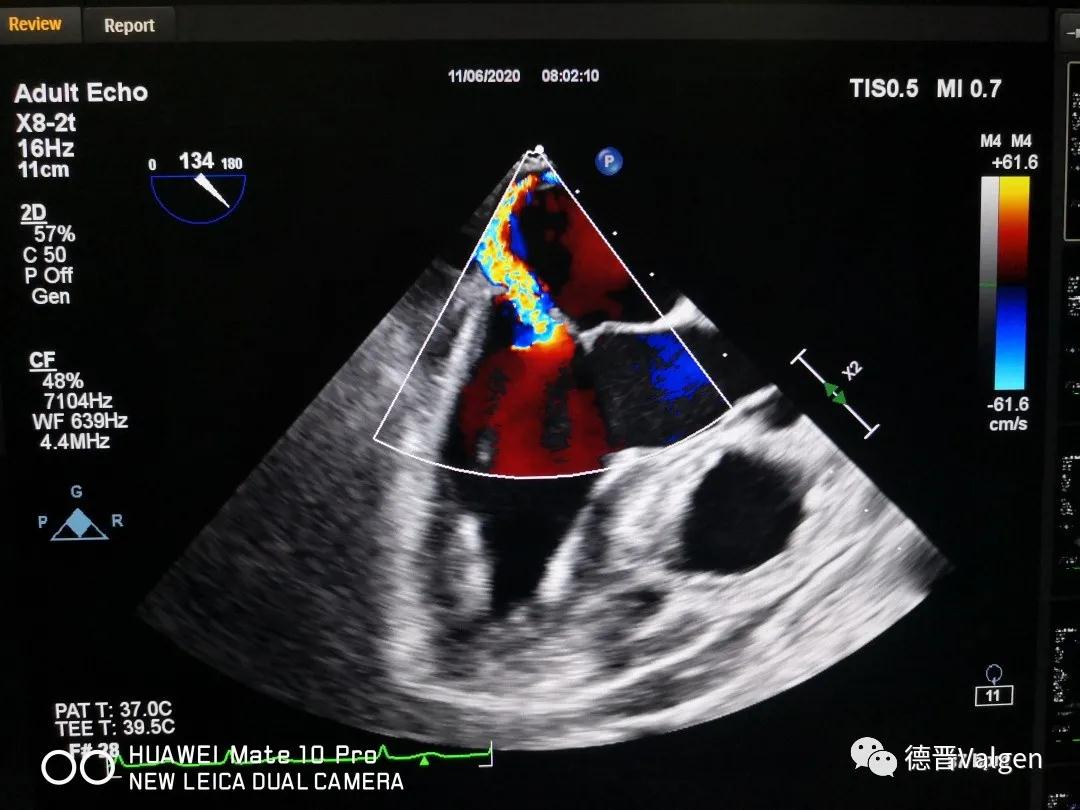

突破!华西医院陈茂教授团队成功开展Dragonfly™手术

德晋医疗专注于结构性心脏病领域尤其是二尖瓣和三尖瓣的相关治疗技术的研发,提供二尖瓣病变系统性解决方案(Tool Box Concept)。德晋医疗曾研发了中国第一款微创介入治疗二尖瓣反流的产品(MitralStitch®),并于2018年1月份成功应用于人体临床。DragonFly™为中国第一款经股静脉二尖瓣缘对缘修复器械,优化的输送系统,使产品可同时应用于三尖瓣介入治疗。德晋医疗成为了国际上唯一具备两种成熟的二尖瓣介入修复器械的公司。德晋医疗的其他二尖瓣和三尖瓣相关器械也在研发当中,公司致力于创新型二尖瓣微创介入治疗全套技术研发,全力推动结构性心脏病治疗领域的发展,让中国智造,惠及世界。